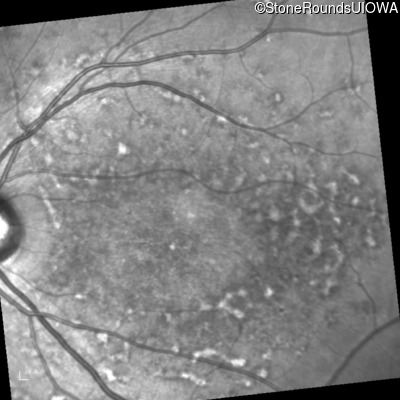

Infrared Fundus Photograph - Right - 20/125 -1

Exemplar

Infrared Fundus Photograph - Left - 20/150

Infrared Fundus Photograph - Right - 20/160 +2

Infrared Fundus Photograph - Left - 20/160 +1